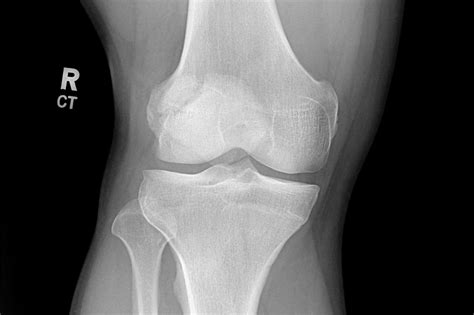

During the typical development of a human skeleton, the patella begins as multiple centers of ossification (bone formation). Usually, these centers fuse together during early adolescence to form one solid, singular bone. In individuals with a Bi Part Patella, this fusion process fails to occur completely, leaving a small accessory bone—most commonly located at the upper outer corner of the kneecap—separated from the main body of the patella.

For many people, this condition is entirely asymptomatic. They may go their entire lives without ever knowing they have a bipartite patella until an X-ray for an unrelated knee issue reveals the anatomical variation. However, for some, the fibrous connection between the main patella and the accessory fragment can become irritated, inflamed, or injured, leading to pain and functional limitations.

⚠️ Note: It is critical to differentiate between a symptomatic bipartite patella and a recent patellar fracture. Unlike a fracture caused by sudden trauma, a bipartite patella typically features smooth, rounded edges on the separated bone fragments, which can be clearly visualized on X-rays.